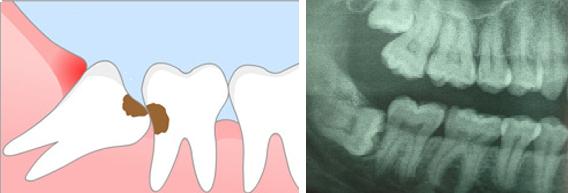

Удаление зубов (удаление корня зуба) – наиболее известная хирургическая манипуляция  для  пациентов среди прочих , проводимых в полости рта. Суть ее заключается в удалении зуба  или его части  из челюстной кости при помощи специальных, адаптированных для разных зубов и разных ситуаций в полости рта инструментов.

• Дистопированные (находящиеся не на своем месте) зубы.

• Сильный наклон зубов, выдвижение,мешающее протезированию или (и) травмирорание рядом лежащих  мягких тканей (характерно для зубов «мудрости»).

• Затрудненность доступа для эффективного лечеия (характерно для зубов «мудрости»).